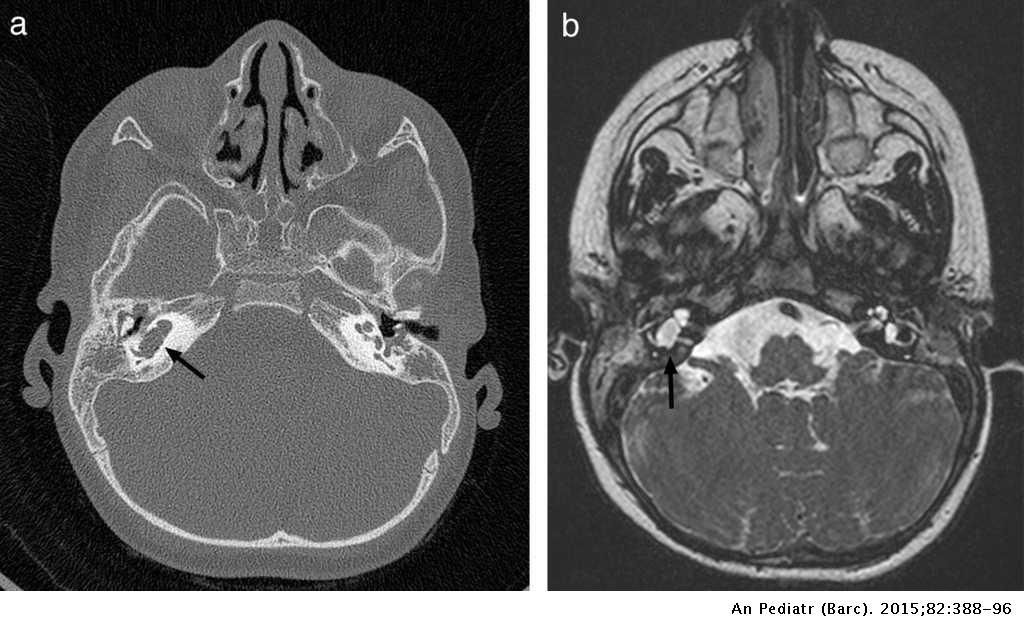

¿Qué vamos a encontrar en la TC de meningitis?

¿Cuál es el mejor estudio de imagen para la meningitis?

¿Cuál es el mejor estudio de imagen para las complicaciones de la meningitis?